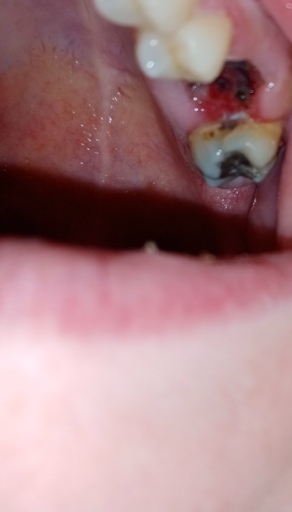

So I have dry socket? Is it infected or healing well? 9 days after wisdom tooth extraction

Hi!! This is my first ever tooth extraction, I’m wondering if I have dry socket ? Or an infection? Or is it healing normally? It’s been 9 days since having my impacted wisdom tooth removed. The place I went to really didn’t give me any information...